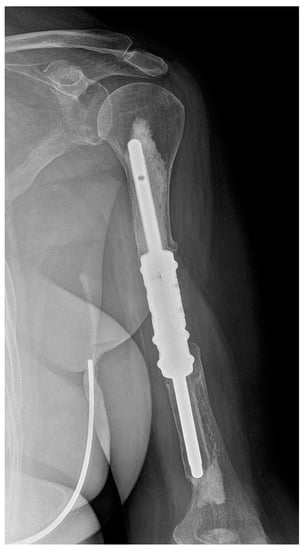

Figure 3.

X-ray image of aseptic loosening of the distal stem of the humeral intercalary endoprosthesis. Resection of the metastasis revealed it was a uterine sarcoma solitary metastatic lesion of the left humerus. After 23 months, there was aseptic loosening. Due to the patient’s poor general condition (pulmonary and multiple skeletal metastases) and acceptable functional result (a Musculoskeletal Tumor Society score of 21), revision was not indicated. This image is from patient 7 in Table 1.

Four of the five cases of type II failure were localised in the humerus (patients 7, 17, 21 and 25) and one in the femur (patient 14). Aseptic loosening occurred on average 21.4 months (range 15–31 months) after surgery and was the most common complication in our study (18.5%). In the group of segmental humeral endoprostheses, there were four cases of aseptic loosening (44.4%): the distal stem in three cases and a single proximal stem in one case (Figure 3). There was only one case (5.6%) of aseptic loosening of the proximal stem of the individual femoral intercalary endoprosthesis. However, in cases of type II failure, no reoperation was indicated due to the general condition of the patient and functional status of the limb. There was a significantly higher risk of aseptic loosening of the diaphyseal implant in the humerus compared with the femur (OR 13.79, 95% CI 1.22–151.05, p = 0.0297).